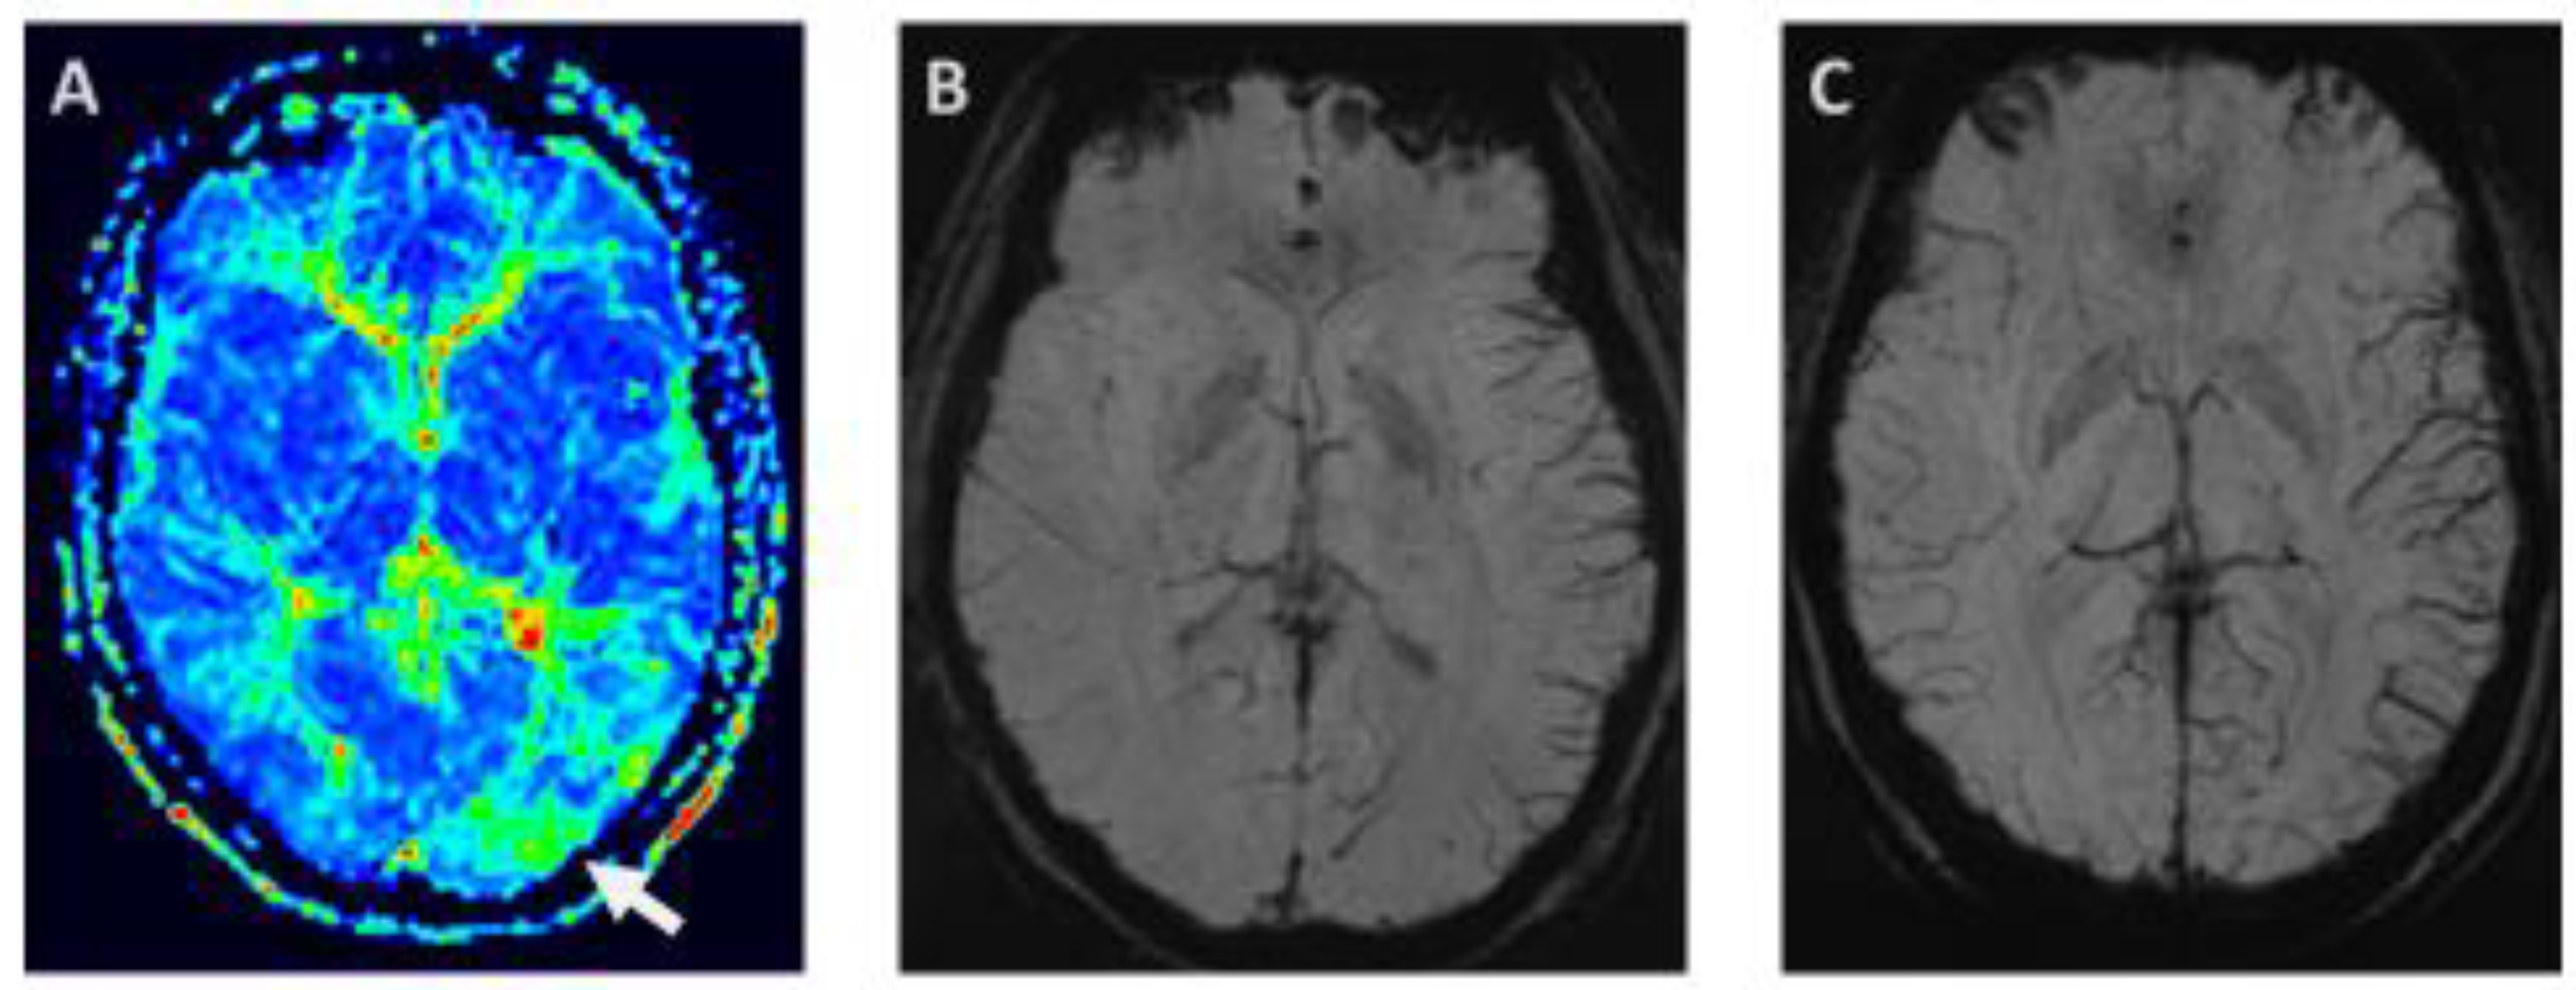

3.4.2. Susceptibility—Weighted Imaging—Prominent focal veins—Index Vein

- Kellner-Weldon, F.; Jossen, M.; Breiding, P.S.; Grunder, L.; Schankin, C.; Scutelnic, A.; Fischer, U.; Muri, R.; Pastore-Wapp, M.; Wiest, R.; et al. Imaging Neurovascular Uncoupling in Acute Migraine with Aura with Susceptibility Weighted Imaging. Clin. Neuroradiol. 2021, 31, 581–588. [Google Scholar] [CrossRef]

- Slavova, N.; Denier, N.; El-Koussy, M.; Wiest, R.; Kellner-Weldon, F.; Fischer, U.; Schankin, C.J. The index vein pointing to the origin of the migraine aura symptom: A case series. Neurology 2020, 94, e2577–e2580. [Google Scholar] [CrossRef] [PubMed]

- Scutelnic, A.; Petroulia, V.; Schraml, L.; Jung, S.; Branca, M.; Beyeler, M.; Fischer, U.; Wiest, R.; Slavova, N.; Schankin, C.J. The “index vein” as a sign for migraine aura in the emergency setting. Cephalalgia 2023, 43, 3331024221132010. [Google Scholar] [CrossRef]